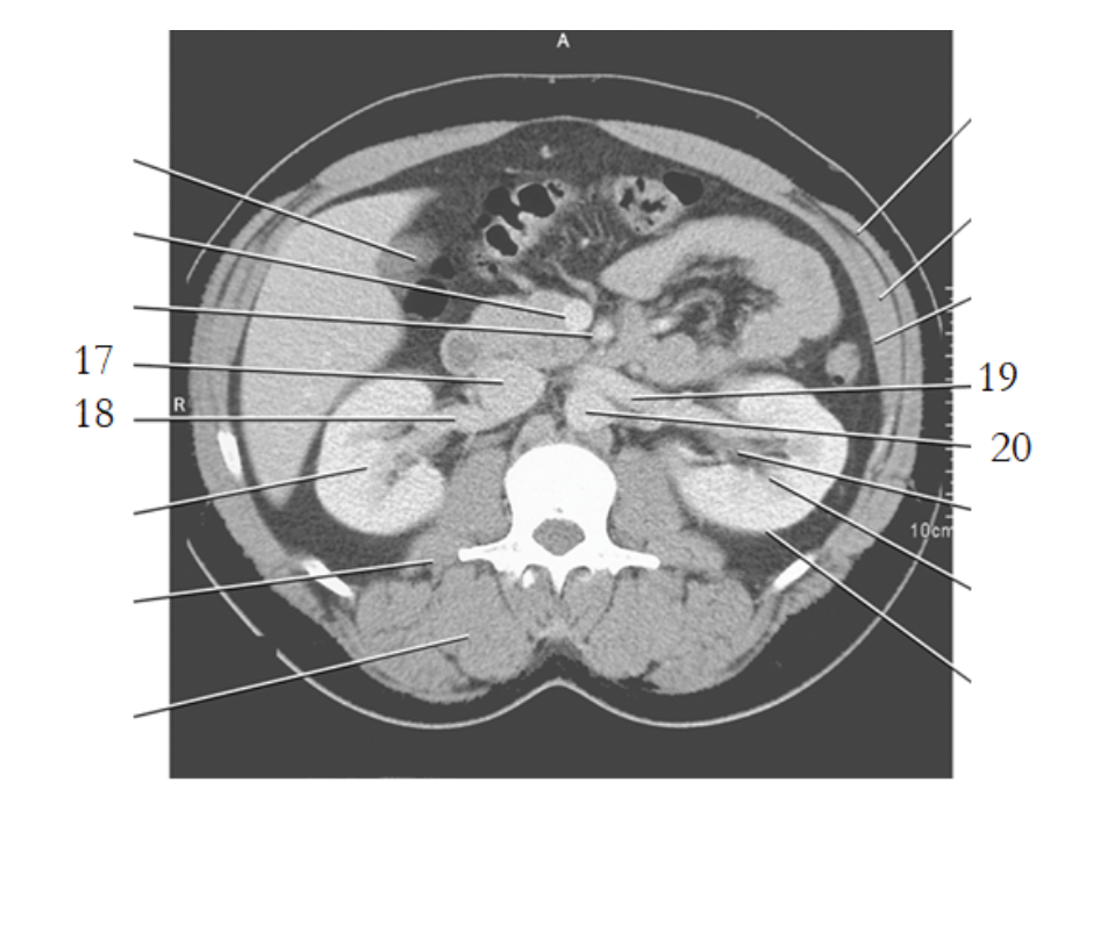

2

aorta

29

pubis

30

ishium

6

ilium

sacral prominatory

4

left common iliac artery

3

ureters

19

greater trochanter

1

cecum

15

femoral head

rectum

14

acetabulum

8

psoas

9

sacram foramen

17

pubic bone

20

prostate

31

seminal vesicles

7

SI joint

28

bladder

pubic symphysis

28 women

cervix

25 women

uterus